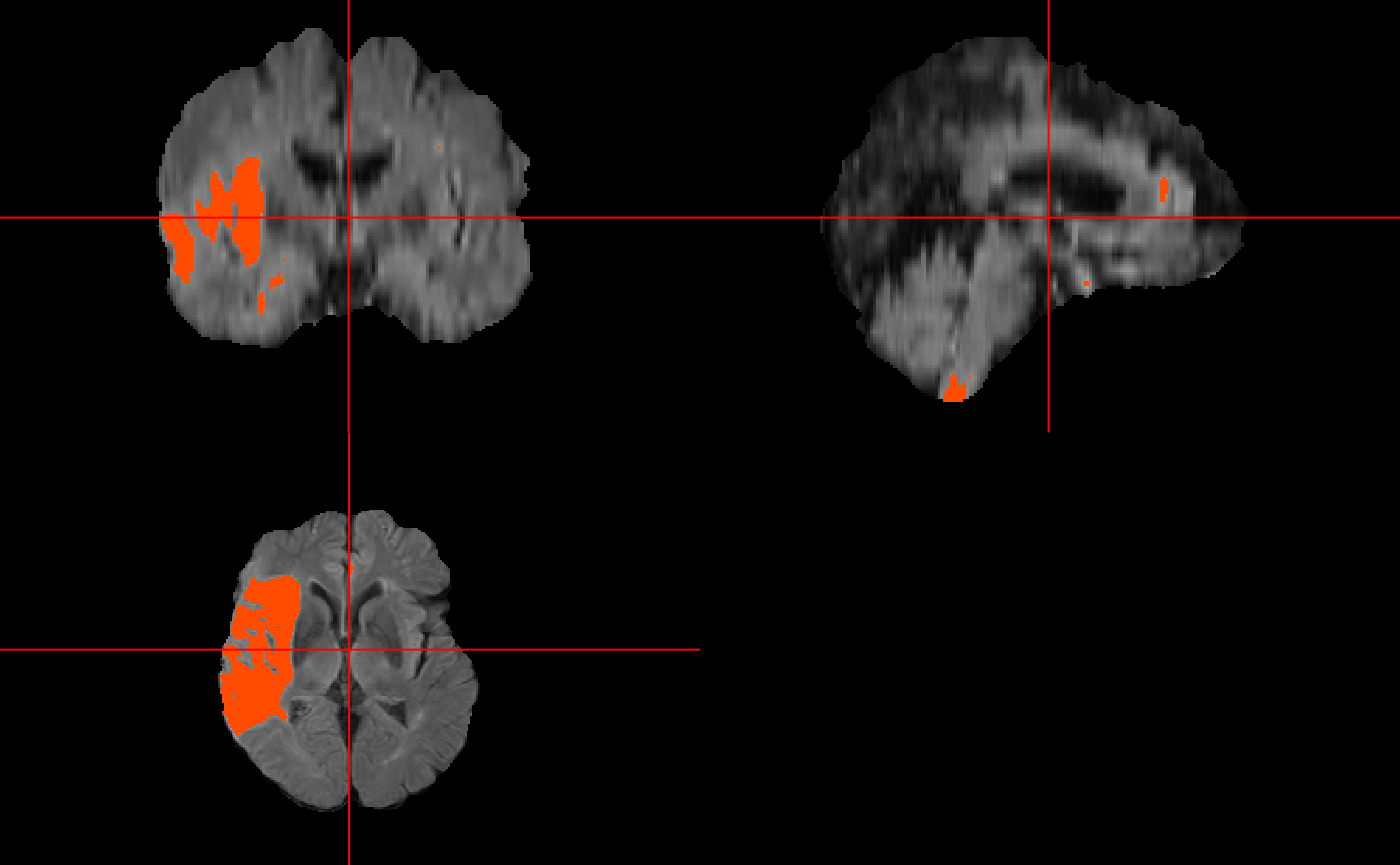

Now, we need to get the model fit for the regression, this fit is then used to create the list of prediction images for each subject. Then I used ortho2() to visualize the prediction image for the first subject.

And now make the prediction image and visualize it…

ortho2(img, test.preds[[1]] > 0.5) #binary prediction